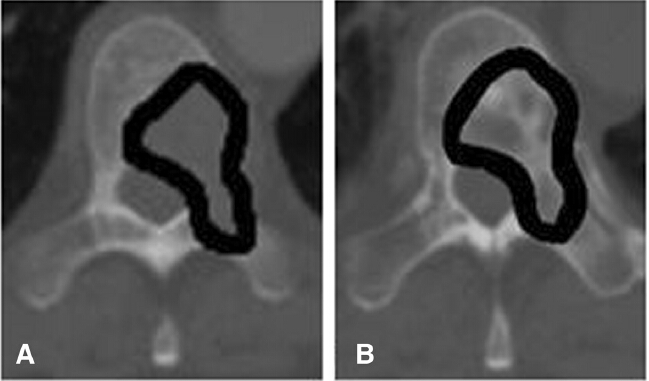

图溶骨性胸椎转移(A)RT前(B)RT后3个月

研究人员回顾分析了135例溶骨性脊椎转移,这些案例来自115名转移性乳腺癌女性,在2000年1月到2012年1月间在相关机构接受治疗。分别在基线,放疗后3个月和6个月,对骨密度进行测量。

分析中的患者中位基线骨密度为194.8HU。3个月时,研究人员发现骨密度比基线时有明显增加,平均为145.8HU(P=0.0001)。同样地,6个月时,平均骨密度增加为250.3HU(P<0.0001)。